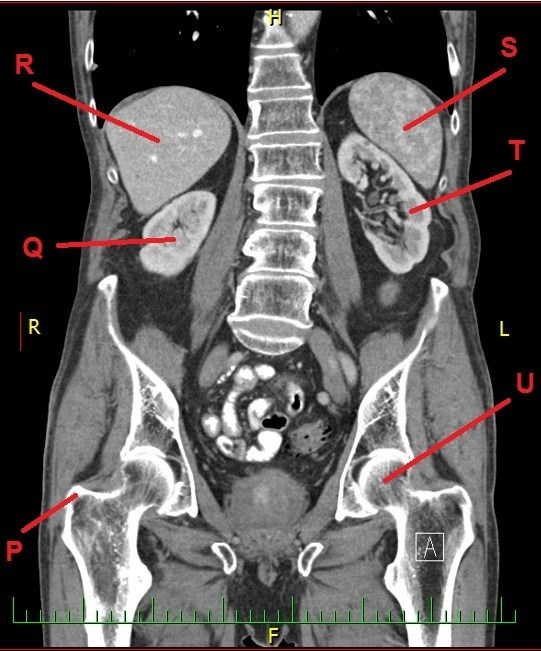

A dál co potřebujete k získání finálních souřadnic? Trocha z té zdravotnické praxe. Správný geokačer má silně vyvinutý smysl pro všímání si detailů, skrytých souvislostí a tak podobně. Princip je jednoduchý. Nepůjde o žádnou kdoví jak složitou matematickou šifru s IT podtextem. V budoucích několika minutách, hodinách či dnech se z Vás stanou radiologové (lékaři zabývající se zobrazovacími technikami) a anatomové. Tak Vás jistě nepřekvapí několik obrázků, na kterých bude vyznačen útvar, který musíte poznat a latinsky (pokud jiným jazykem, tak Vás na to upozorním) pojmenovat. Myslím, že vše bude jasné. Tak jdeme na to…

P - počet písmen v názvu útvaru (latinsky, 3 slova)

Q - počet písmen v názvu útvaru/orgánu (latinsky, 1 slovo)

R - počet písmen v názvu útvaru/orgánu (řecky, 1 slovo)

S - počet písmen v názvu útvaru/orgánu (řecky, 1 slovo)

T - počet písmen v názvu útvaru/orgánu (řecky, 1 slovo, prosím použít "f" místo "ph")

U - počet písmen v názvu útvaru (latinsky, 2 slova)